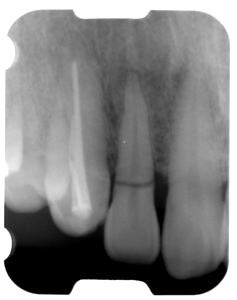

前歯即時埋入症例

術前術前主訴-前歯が腫れて痛い。治療法のうち、ブリッジとインプラントを説明して隣の前歯を削らないですむことからインプラントを選択された。 術前レントゲン術前レントゲン術前レントゲン 抜歯抜歯抜歯を行う。折れていた位置がかなり深い位置であるのがわかる。 歯根も抜歯歯根も抜歯

歯根も抜歯歯根も抜歯歯根も抜歯 抜歯した穴をよく掃除抜歯した穴をよく掃除抜歯した穴をよく掃除(掻爬)後すぐにインプラントを埋入 埋入直後のレントゲン埋入直後のレントゲン埋入直後のレントゲン。上部に見えるのは抜いた歯を利用して両どなりの歯に接着して一時的に使えるようにした。 二次オペ時二次オペ時

仮の支柱を装着仮の支柱を装着仮の支柱を装着 作業模型上のセラミック上部構造作業模型上のセラミック上部構造作業模型上のセラミック上部構造 術後術後術後